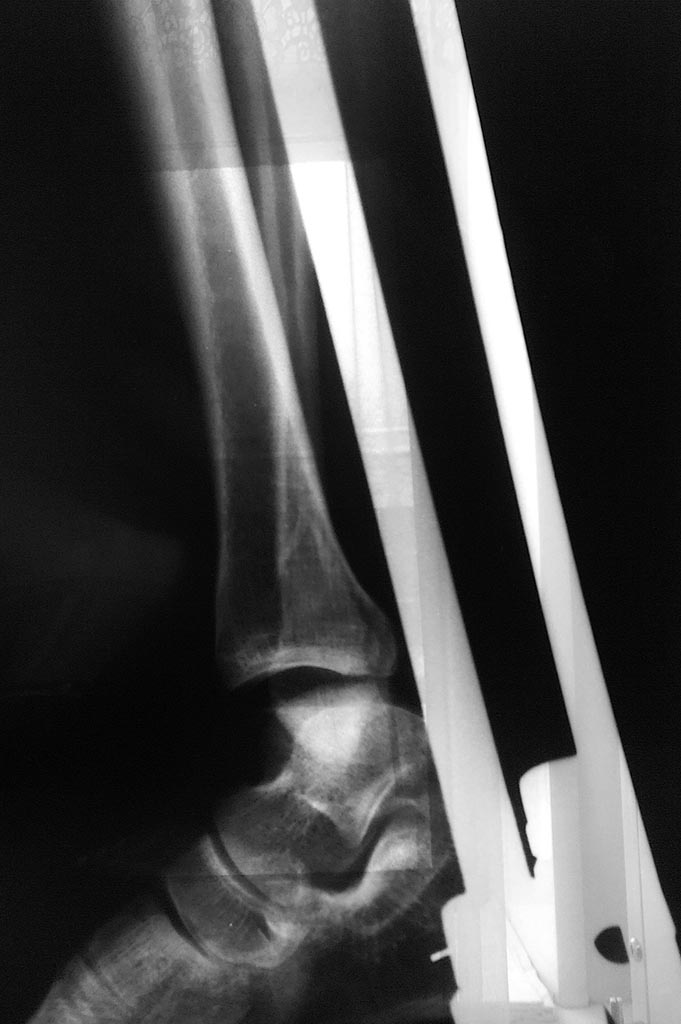

[Ortho] Лодыжки - подвывих стопы?

Имя     : 1.jpg

Url     : http://weborto.net:8080/pipermail/ortho/attachments/20180225/ed17c2c1/attachment-0002.jpg